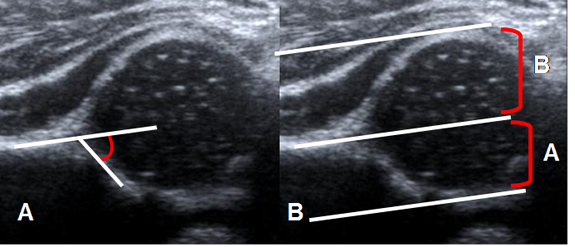

Fig 33 B. Displasia de cadera.

Ecografía. A: Disminución del ángulo alfa (50º) y B: Disminución de la relación A/B, por displasia.